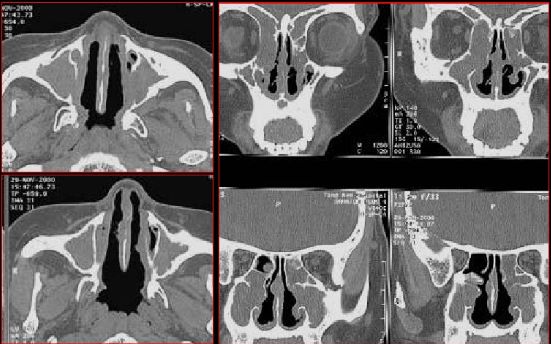

慢性多发鼻窦炎鼻息肉

慢性多发鼻窦炎—MRI